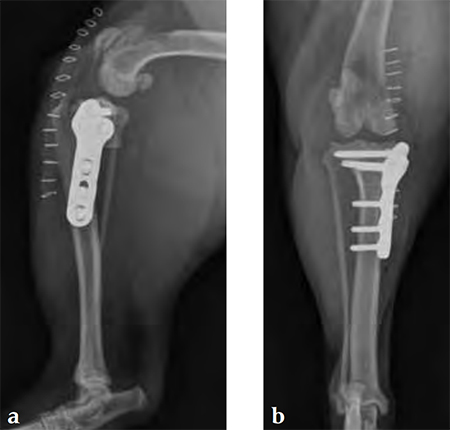

Case 1: English bulldog

(Case provided by Brian Beale, Houston, USA)

A 4-year-old, female, spayed, 33 kg English bulldog had a CrCL tear and a medial patellar luxation. The small stature 3.5 mm TPLO plate was perfect for this dog due to the small profile of the bone and the need to use a heavier plate (3.5 vs a 2.7 mm). In the past, veterinary surgeons have been forced to either squeeze the standard TPLO 3.5 mm plate on the bone or use an undersized TPLO 2.7 mm plate. In this patient, the shorter and smaller profile head of the small stature TPLO 3.5 mm was perfect.